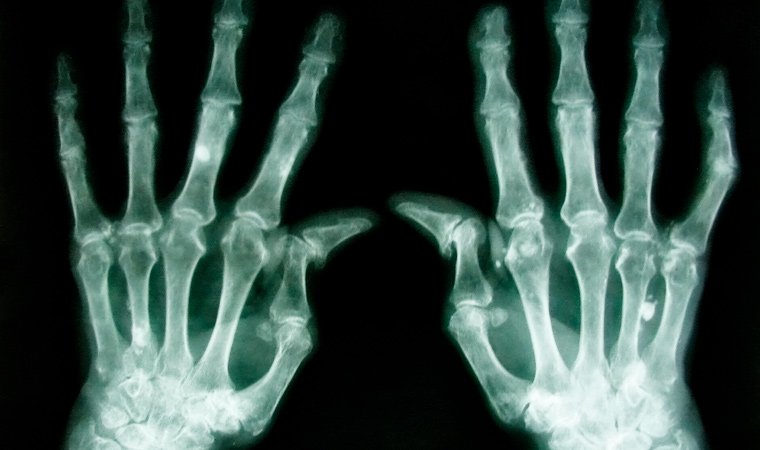

Данное наименование объединяет целую группу заболеваний, при которых развивается воспалительный процесс в суставах, сопровождаемый деформацией.

- Ревматоидный – проявляется в виде поражения мелких суставов.

Все виды артритов сопровождаются болью, вынужденной ограниченностью движений и дальнейшей деформацией в месте локализации патологического процесса.